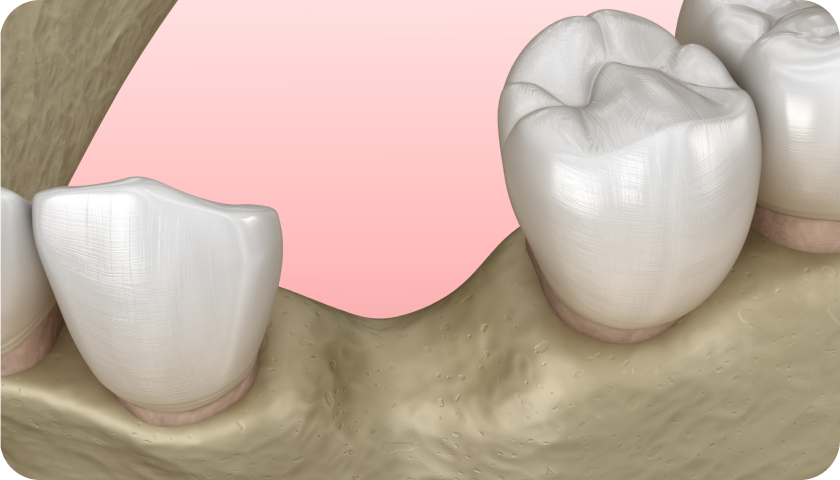

La greffe osseuse est un acte dentaire régulièrement réalisé pour combler un ou plusieurs trous localisés dans l’os de la mâchoire. Différentes causes peuvent amener à ce type de situations :

- Perte d’une ou plusieurs dents,

- Maladies parodontales type gingivite,

- Traumatismes,

- Malformation osseuse…

D’un point de vue esthétique mais aussi pratique, les dents perdues peuvent être remplacées par des implants dentaires. Pour pouvoir les poser, il faut auparavant combler le creux présent dans l’os de la mâchoire, pour pouvoir y apposer la vis de l’implant. Le Dr Bénichou vous accompagne dans cette procédure, pour une greffe osseuse dentaire à Toulouse de qualité professionnelle.